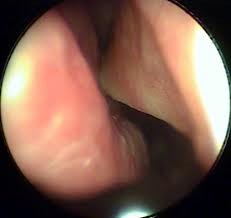

Инородное тело глотки

Инородное тело в глотке – это чужеродный предмет, который попал в ее полость. Обычно инородные тела попадают вместе с едой, это могут быть кости, кусочки дерева, шелуха, реже – булавки, зубные протезы, гвозди. Также большие куски пищи при плохом пережевывании либо спешном проглатывании могут перекрывать вход в гортань, вызывать удушье. Читать далее